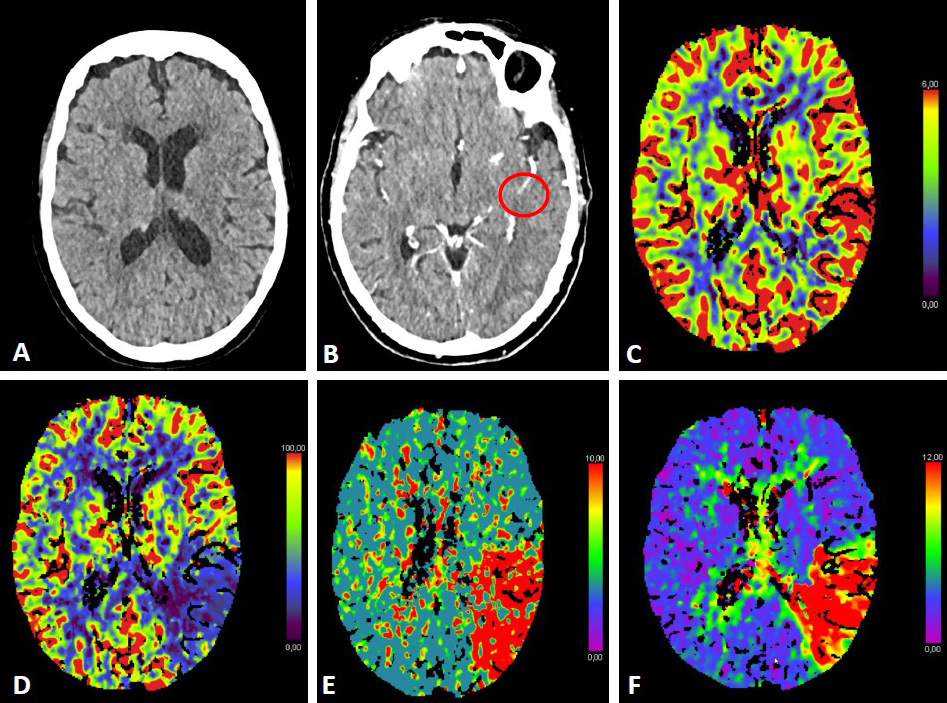

The use of additional perfusion imaging (CT-P or MR-P) in the early time window (within 6 hours of symptom onset) is controversial and is not recommended in routine clinical practice [34, 35, 36, 37]. Perfusion imaging can be used to estimate the infarct core and potential tissue at risk (penumbra). Fig. 2 (Ref. [38, 39, 40]) illustrates CT-P parameters and potential thresholds for both the infarct core and penumbra. These thresholds are debatable and not universally accepted, and may change with the duration of symptoms [38, 40]. In an early time-window, CT-P can overestimate the infarct core, possibly because of a lack of contrast arrival overall [41]. In a pooled analysis from the Highly Effective Reperfusion evaluated in Multiple Endovascular Stroke Trials (HERMES) collaboration, adding CT-P in an early time window has not been found to be associated with functional outcomes [37].

Fig. 2.CT-Perfusion. NCCT ASPECTS 10 (A). CT-A with M2-occlusion (B).

Interpretation of CT-P: the cerebral blood volume (CBV) is symmetrical without a

regional decrease (C). Cerebral blood flow (CBF) is reduced in the posterior MCA

territory on the left (D). The mean transit time (MTT) of the contrast agent (E)

and Tmax (time to maximum; time delay between the contrast agent arrival in the

proximal large vessel arterial circulation and the brain parenchyma perfusion

[F]) are prolonged. The infarct core in CT-P shows a markedly reduced CBF (